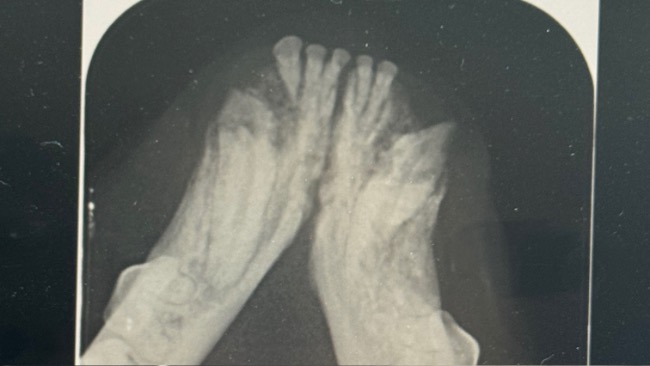

Czy widzicie tego wielkiego kota wyglądającego jak mieszanka z rysiem? Jest wielkim słodziakiem i jednocześnie straszna ciapa. Mimo tego że mieliśmy już nie przejmować więcej kotów ze względu na kiepską sytuację finansową, nie umiałyśmy mu odmówić pomocy. Badania krwi wyszły dobrze, testy na choroby zakaźne ujemne, mogliśmy przystąpić do działania. Został wykastrowany, amputowaliśmy porażony ogon oraz wykonana została z sanacja jamy ustnej z ekstrakcja połamanych zębów. Teraz dochodzi do siebie po zabiegu w domu tymczasowym i tęsknie wypatruje swojego prawdziwego domu. Jest przytłoczony ilością kotów w domu tymczasowym, potrzebuje spokoju. Nie pozwolimy mu wrócić na ulicę, los się do niego uśmiechnął, a my mu pomożemy. A ty pomożesz ?